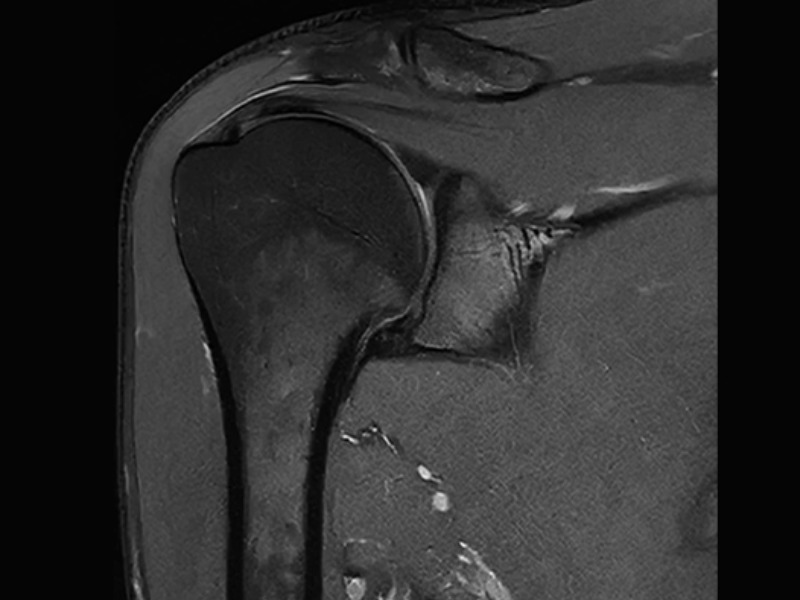

PD Shoulder with uAI DeepRecon